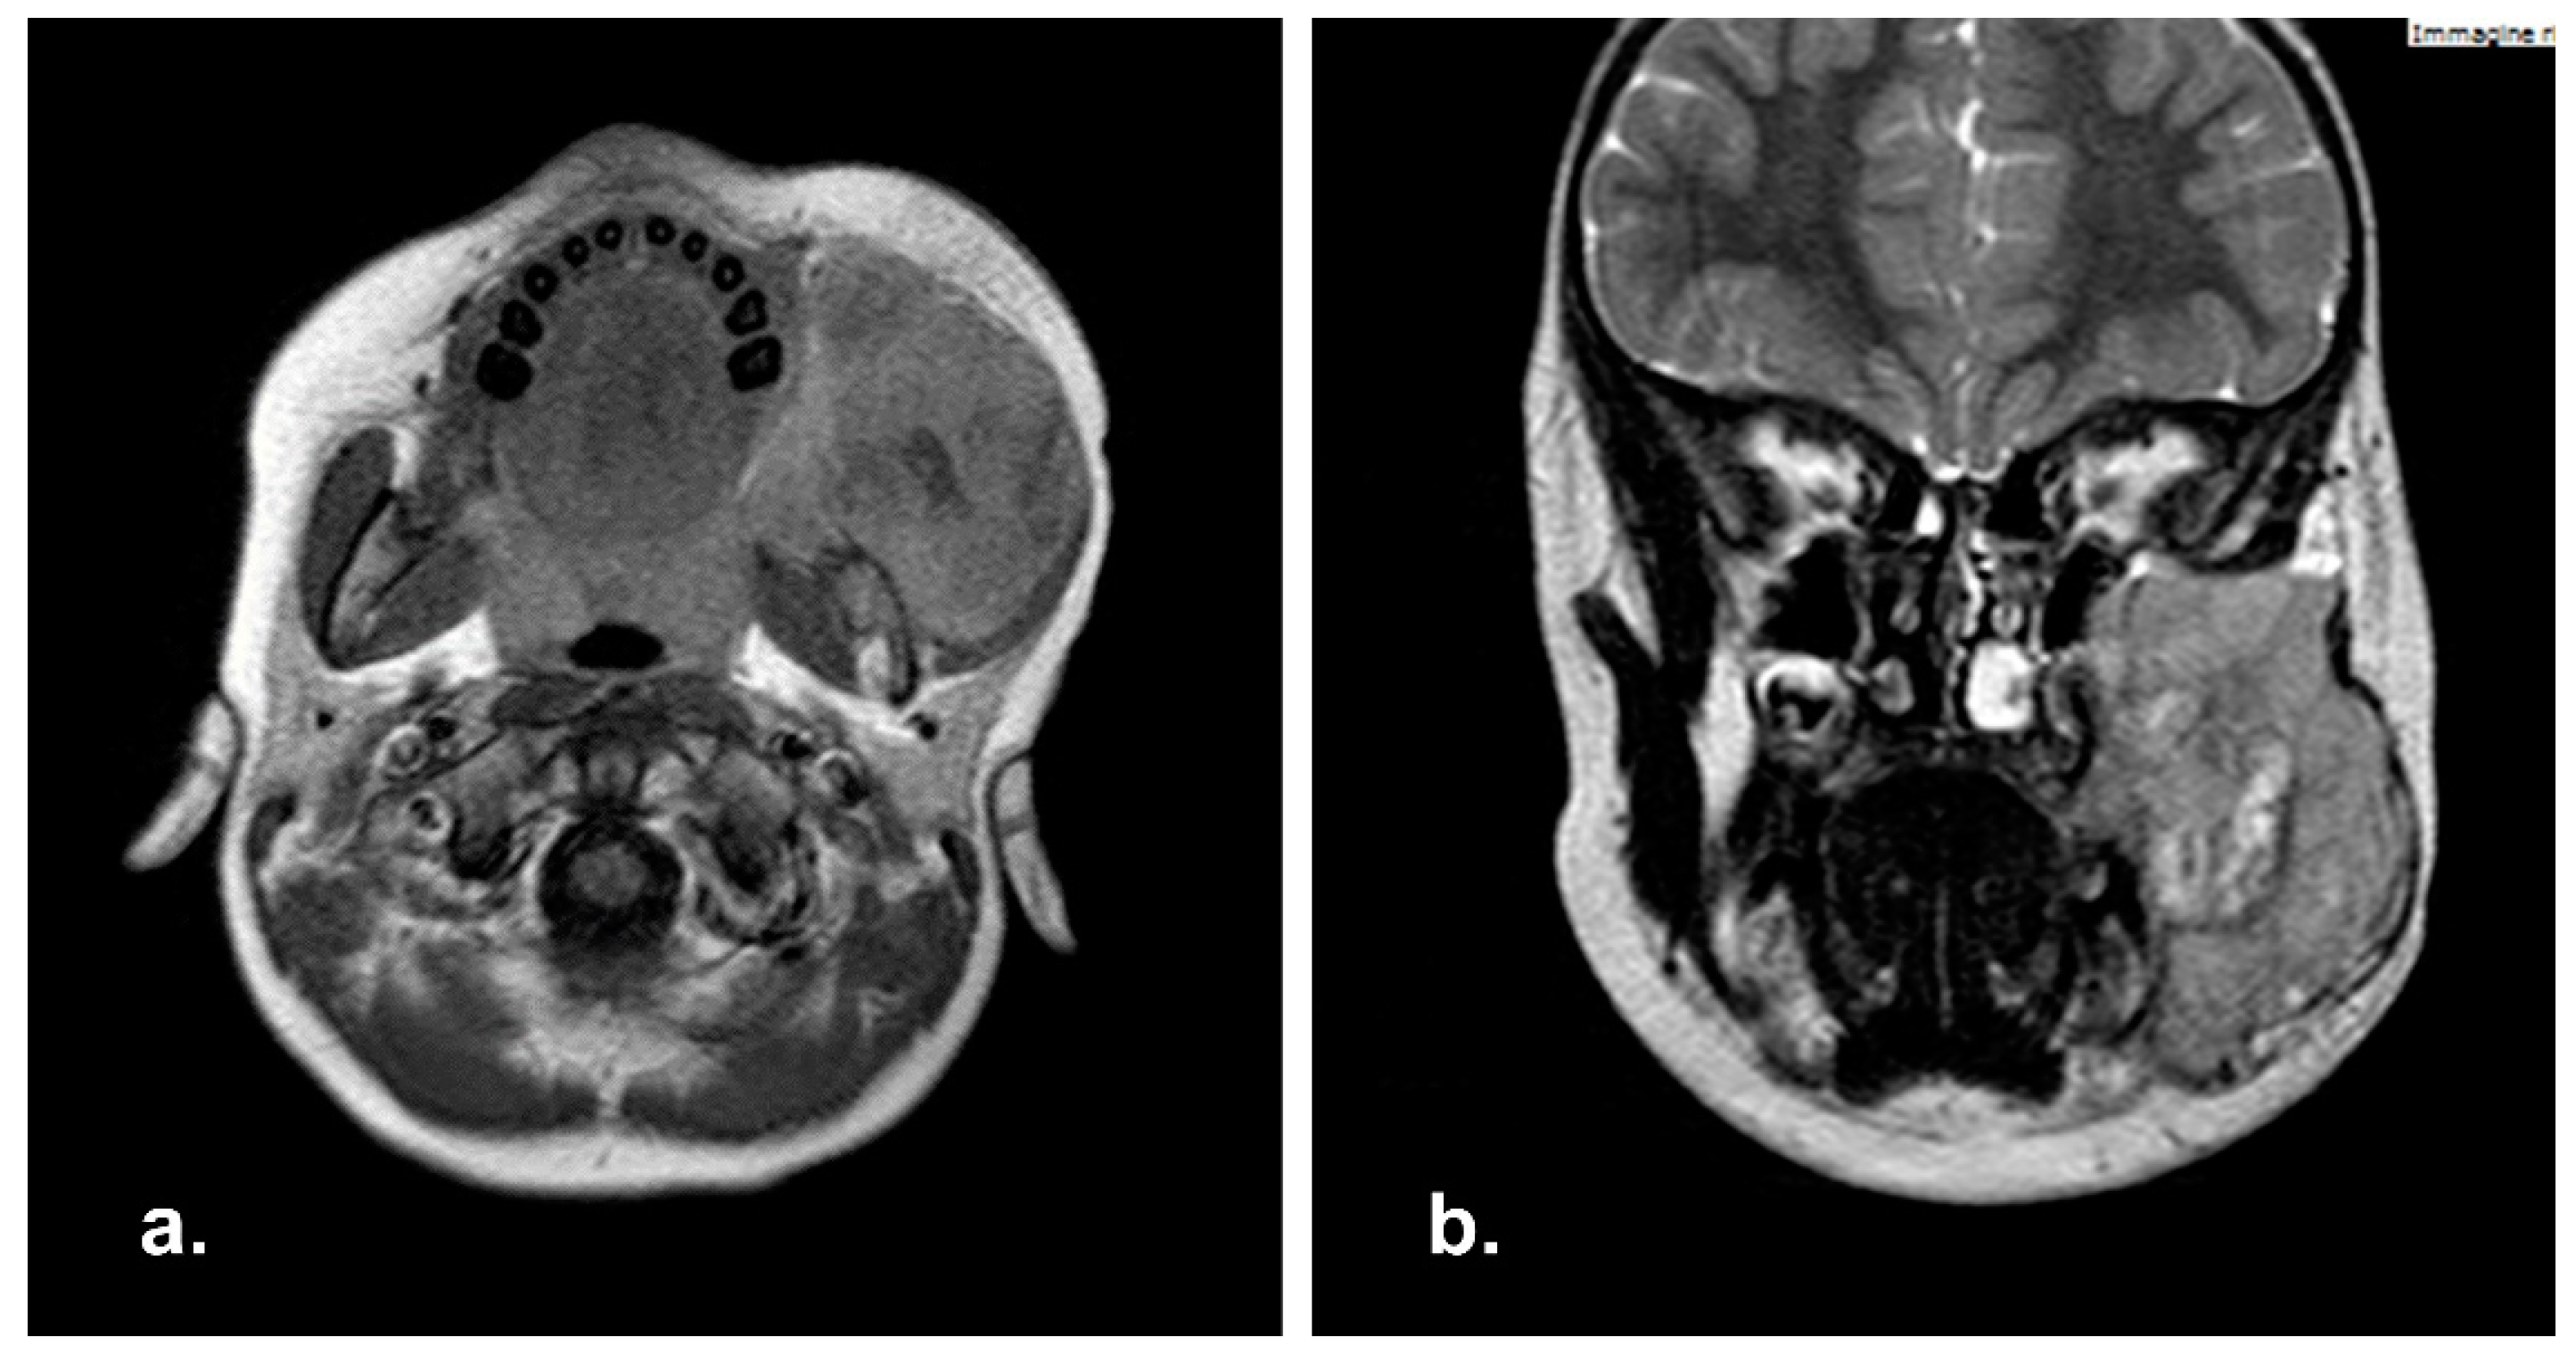

A 3 years-old male referred to Pediatric Oncology in January 2014 complaining of superior eyelid edema and bilateral exophtalmus. The patient was in good general condition. The MRI study showed a naso-ethmoidal mass with intraorbital extension. There were also bony defects in the right medial orbital wall and floor. Additionally, the contralateral orbit was also partly involved (Figure 4).

Figure 4. Pre-operative Computed Tomography scan (CT) showing an ethmoidal mass involving the nasal septum and bilateral lamina papyracea. (a) Bone and (b) soft tissue CT algorithm.